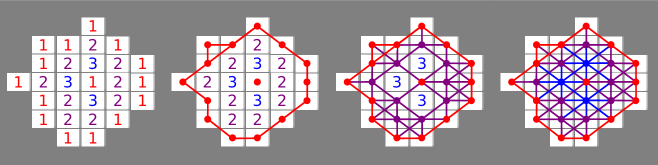

As each vertex is associated with a pixel in the original image, it is natural use the pixel intensity (i.e., the grayscale value of each pixel) to assign a value to each vertex. This forms the basis of what we will call the intensity filtration. A toy example of the increasing intensity filtration is shown in Figure 5(a). The colors represent the point in the filtration when the vertices and edges are added (we do not shade triangles for aesthetic reasons).

We define an additional filtration by associating the distance from the lesion border, as given by the radiologist, to each pixel. We call this the border filtration. The increasing border filtration produces an ‘annulus’ which grows until it fills the lesion. The decreasing filtration produces a misshapen ‘disc’ which expands from the center of the lesion. While this is clearly not topologically useful for classification, in practice the combination of the border filtration with the intensity filtration gives better classification results than using the intensity filtration alone.

To simplify the computational difficulties encountered with two-dimensional filtrations, we use one-dimensional filtration slices to approximate the two-dimensional filtrations. Let represent the border filtration and represent the pixel intensity filtration. We divide the range of the border-filtration into 20 equally spaced slices. At each slice , we use the intensity filtration to compute the persistent homology of the subcomplex . This gives rise to the filtered complex .